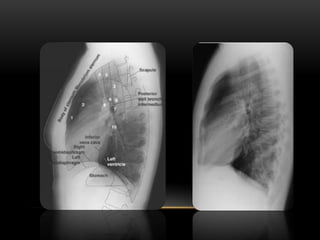

Técnica de Teleradioradiografia de tórax y lateral.

T : Tráquea

C: Clavículas

AE: Apófisis Espinosa

BD y BI: Bronquio derecho e izquierdo.

Ba: Botón Aórtico.

VCS: Vena cava superior

AP: Arteria Pulmonar.

AD: Aurícula Derecha.

VCI: Vena cava inferior.

VI: Ventrículo izquierdo

CF : Angulo costo frénico

DD y DI : Cúpula diafragmática

derecha e izquierda.